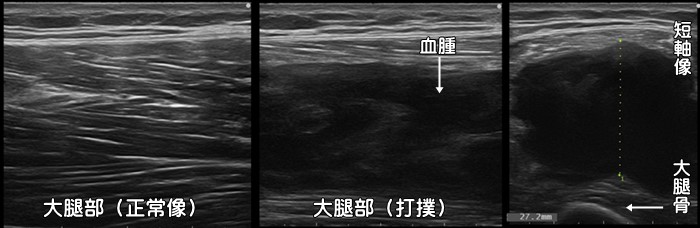

打撲・血腫

自転車での転倒や階段からの転落、またコンタクトスポーツによる打撲でしつこい痛みが続く場合、筋肉内に出血が起こっている可能性があります。筋肉は筋膜によって包まれていますが、筋膜外であれば体表から容易に青あざとして確認できます。しかし筋膜内での出血の場合には体表からは分からない事があります。上記のエコー画像でも筋肉内に黒い血腫が確認できますが、体表からは全くわかりませんでした。